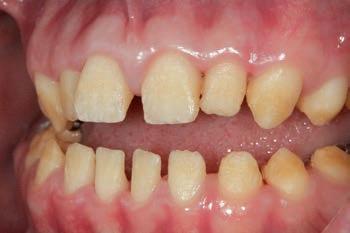

Clinical case

The patient was an 18-year-old male with a confirmed family history of Xlinked AI, who was otherwise in good health and non-smoking. Upon initial clinical presentation, a low-caries-risk, complete adult dentition from second molar to second molar was present, which was globally affected by pitted, hypoplastic and hypomineralised AI, dento-alveolar disproportion and an unusual generalised open occlusion, characterised by one occlusal contact at the right first molar region in the maximum intercuspation position (MIP). Historical paediatric management of the dentition involved placement of stainless steel crowns at the first permanent molar sites to protect the emerging dentition from post-eruptive breakdown and loss of occlusovertical dimension during the mixed dentition phase.6 On adult presentation, all but the UR6 stainless steel crown remained intact. Oral hygiene was poor, with evidence of plaque-induced chronic gingivitis (Figure 1). The patient reported experiencing severe, widespread hypersensitivity upon hot, cold, osmotic and masticatory stimuli, and feeling aesthetically self-conscious. The patient was seeking comprehensive fixed prosthodontic care and was well informed about the nature of such treatment, having witnessed his elder siblings undergo similar treatment.

1: The patient’s initial situation on clinical presentation to the tertiary care referral centre. The dentition is globally af fected by amelogenesis imperfecta, associated with dentoalveolar disproportion and an unusual presentation of open occlusion.